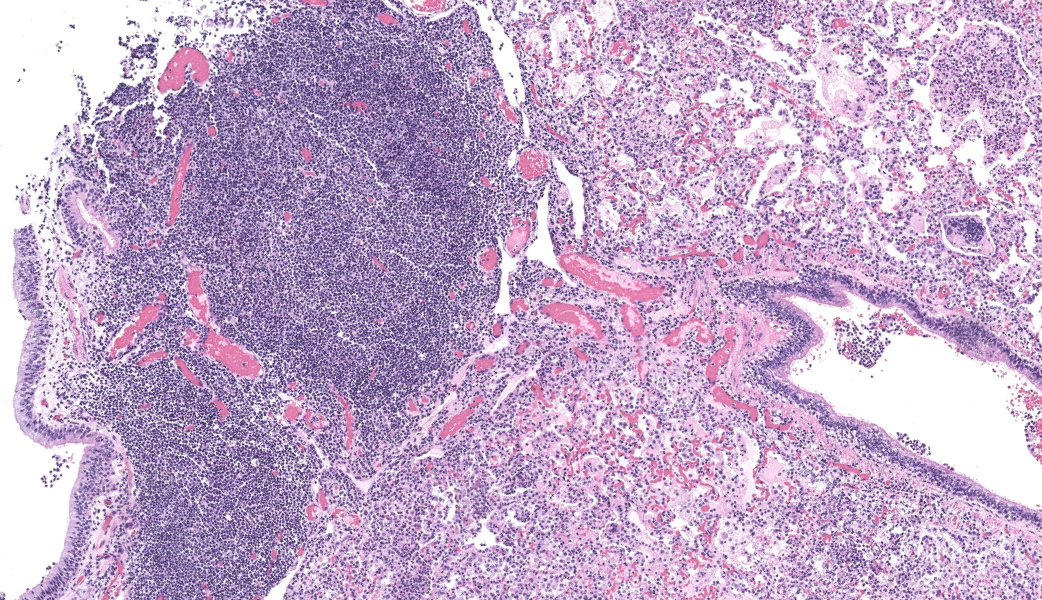

Lung, multiple sections. Within a single section of lung, approximately 75% of the bronchial, bronchiolar, and alveolar lumina contain overall large numbers of neutrophils, macrophages, large multinucleated cells, cellular debris, homogenous eosinophilic material, fibrillary eosinophilic material, and occasionally scattered erythrocytes. The multinucleated cells are often large and bizarre in appearance, some containing approximately 40 nuclei. The cytoplasm of these multinucleated cells is eosinophilic and variably granular to homogenous. A subset of these multinucleated cells contains few distinct optically clear vacuoles, while others demonstrate phagocytosis of few neutrophils. There is mild vascular congestion throughout, and there are small clusters of lymphocytes cuffing airways multifocally.Contributor's Morphologic Diagnoses:

Pneumonia, bronchoalveolar, suppurative, histiocytic, focal, subacute, severe with intraluminal multinucleated giant cells.Contributor's Comment:

Lung: Bronchopneumonia, histiocytic and neutrophilic, chronic, multifocal to coalescing, severe, with numerous multinucleated giant cells.JPC Comment:

Our fourth conference this year was moderated by the esteemed Dr. Thomas Cecere from Virgina Tech. The JPC team was thrilled to have him back for the second year in a row. This first case provided a great discussion on diagnostic workups and the processes that the pathologist should consider when choosing next steps in a case. Here, the lungs were “chock-a-block” full with histiocytic and neutrophilic inflammation with numerous giant cells that one participant remarked as having “a million nuclei.” These were some of the most impressive giant cells that many participants had seen. The bacteria were very difficult to see on the H&E, but the pattern of inflammation and presence of such robust giant cells should clue one into the presence of infectious organisms. As such, next steps should include a full gamut of routine infectious organism stains, including gram stains, acid fast stains, and fungal stains (GMS, PAS). Given that these were performed by the contributor, only confirmatory GMS and Fite-Faraco (FF) stains were performed in house, which revealed weakly acid-fast, GMS-positive organisms within multinucleated giant cells. This is consistent with the Nocardia spp. that were identified by the contributor. Those “chef’s kiss” multinucleated giant cells, though, deserve some recognition here.The multinucleated giant cell macrophage is a truly remarkable physiologic phenomenon. How they are formed is poorly understood. The current understanding is that macrophages need to be present in chronic inflammation, where they are constantly exposed to pro-inflammatory cytokines, such as IFN-γ, IL-3, IL-4, IL-13, and GM-CSF, as well as pathogen-associated molecular patterns (PAMPs) and other mediators of inflammation.1 A common setting in which these “ingredients” are found is in fungal infections or when dealing with foreign bodies, both of which can sometimes be too large for inflammatory cells to phagocytose and handle on their own. In this environment, macrophages will be in close association with one another and will begin to express molecules on their cell surface that enable fusion with one another, including dendritic cell-specific transmembrane protein (DC-STAMP; major driver of fusion), β1 and β2 integrins, CD44 (hyaluronic acid receptor), CD47 (integrin-associated protein), macrophage fusion protein receptor (MFPR), fusion regulatory protein (FRP-1, also known as CD98), and P2X7 (an ATP-activated ion channel that results in pore formation).1